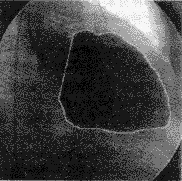

图3显示了本文基于自适应方向滤波所得到的左心室轮廓,图像分辨率为1024×1024×10bits。初始脊点数均为4。

(a)ED

(b)ES

图 3 ADF得到的左心室轮廓(a)和(b)为左心室的ED(舒张末期)和ES(收缩末期)